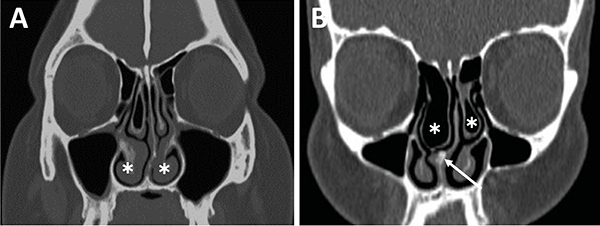

Respecto a los ostium esfenoidales, cabe destacar que son el punto de entrada óptimo al seno esfenoidal. En caso de ser dificultosa su localización (situación frecuente) se podría ingresar al seno esfenoidal aproximadamente 1,5 cm por encima del borde superior de la coana (fig. 11).23,13

El grado neumatización del seno esfenoidal se puede clasificar en selar, pre selar y conchal (fig. 12).1,29,30,58 En el tipo conchal, el área bajo la silla turca es de hueso sólido sin neumatización. En el tipo preselar, el área neumatizada no penetra más allá del plano perpendicular de la pared selar. En el tipo selar, presente en el 86% de los individuos, la región neumatizada se extiende al cuerpo del esfenoides bajo la silla turca, pudiendo extenderse hacia posterior. Esta característica del seno es importante ya que ante la presencia de un tipo conchal es recomendable la utilización de neuronavegación.23,58

Figura 11: Ostium esfenoidales identificables en TC. A) TC corte axial; B) TC corte sagital.

Figura 12: Neumatización del seno esfenoidal en TC cortes sagitales. A) Tipo selar; B) Tipo preselar; C) Tipo conchal.